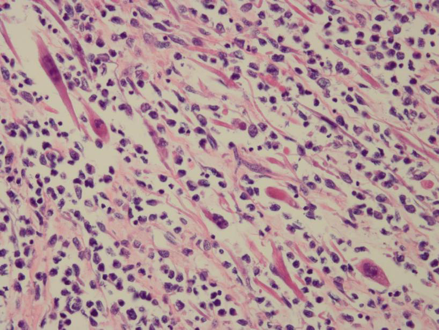

5.血管肉瘤(hemangiosarcoma)

血管肉瘤起源于血管内皮细胞,有时又称恶性血管内皮瘤,可发生在各器官和软组织。发生于软组织者多见于皮肤,尤以头面部为多见。

血管肉瘤一般恶性程度较高,常在局部淋巴结、肝、肺和骨等处形成转。

(2)镜下观

分化好者瘤组织形成大小不一,形状不规则管腔,肿瘤性血管内皮细胞有不同程度异型性,可见核分裂像;分化差者瘤细胞常呈团片状增生,血管腔可不明显,瘤细胞异型性明显,核分裂像多见。免疫组化显示第八因子和CD34阳性。

血管肉瘤:瘤细胞异性型非常显著,可以看见血管腔。